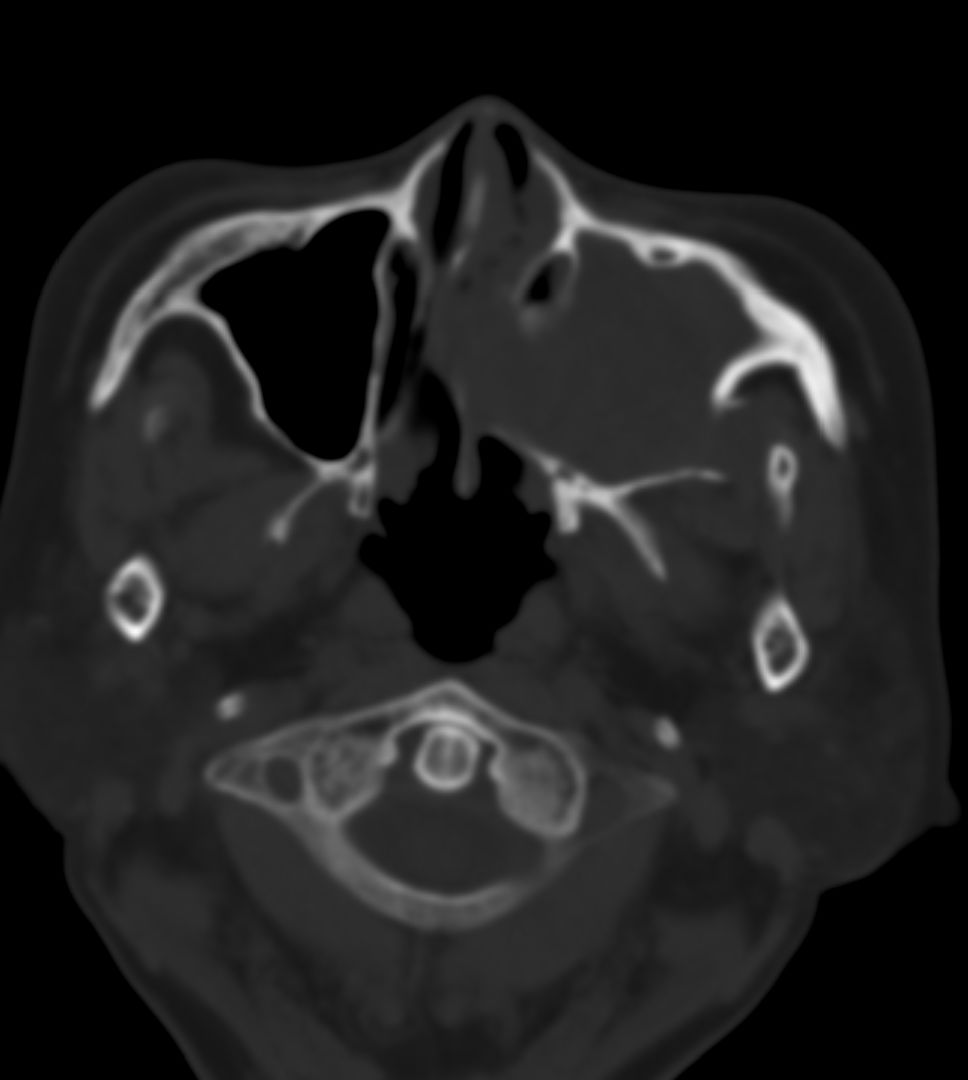

女,69岁。鼻出血2月多。(会诊病史就这样简单)鼻副窦ct检查如下:

左侧鼻腔及上颌窦见软组织块影,左侧上颌窦腔扩大,骨质吸收,右侧上颌窦见半圆形软组织密度影,鼻中隔向右侧弯曲,左侧鼻和鼻窦内翻型乳头状瘤可能性大,建议增强。

左侧上颌窦及鼻腔内见软组织密度影,其内密度不均匀,见斑片状高密度影,右侧上颌窦腔明显扩大,窦壁吸收变薄,鼻中隔右偏,右侧上颌窦见一半圆形软组织密度影,边界清楚,其内密度均匀。诊断,1、左侧鼻腔及上颌窦内翻乳头状瘤可能性大,上颌窦癌,息肉及霉菌性上颌窦炎待除外。2、右侧上颌窦粘膜下囊肿。

1)考虑左侧上颌窦内翻乳突状瘤突入左侧鼻腔。2)副鼻窦炎,右侧上颌窦黏膜下囊肿。

病理:霉菌性左侧上颌窦炎伴左侧上颌窦纤维组织增生。

窦腔密度不均匀增高,无明显钙化征象,后外侧及内侧窦壁膨胀明显,局部破坏消失,筛窦受累及,但双侧对比发现左侧窦壁骨质有硬化增白现象,这可能是支持左侧霉菌性上颌窦炎的主要依据点。